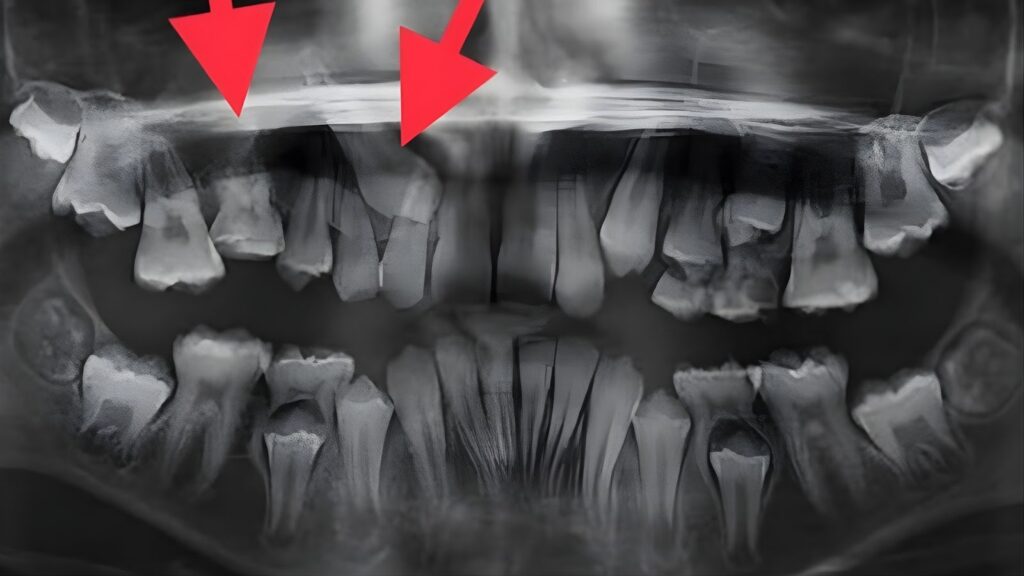

Every child begins with a complimentary consultation that includes facial photos, intraoral photos, and a panoramic X ray that allows Dr. Freeman to evaluate structures below the surface. This comprehensive evaluation forms the foundation of a customized treatment plan.